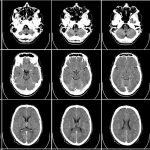

Programda tıpta kullanılan görüntüleme sistemleri ele alındı. İyonize radyasyon nedir? Röntgen, MIR, tomografi, PET/CT gibi birçok farklı teknolojinin fiziği konuşuldu.